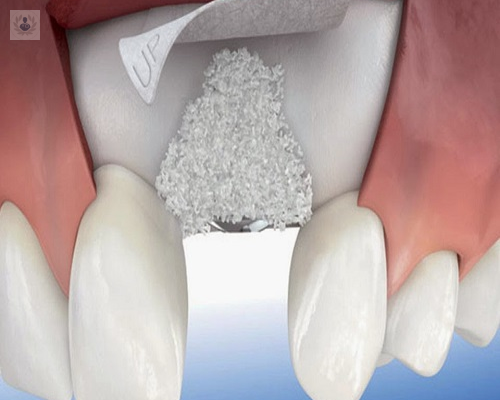

¿Cómo funcionan los Injertos Óseos y la Regeneración para tratamientos de Implantología Oral?

El mejor injerto proviene del mismo paciente, pero en algunas ocasiones no hay suficiente y es preferible utilizar Injerto Óseo procedentes de banco de hueso.